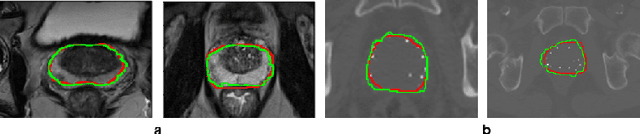

Abstract:Deep learning has shown unprecedented success in a variety of applications, such as computer vision and medical image analysis. However, there is still potential to improve segmentation in multimodal images by embedding prior knowledge via learning-based shape modeling and registration to learn the modality invariant anatomical structure of organs. For example, in radiotherapy automatic prostate segmentation is essential in prostate cancer diagnosis, therapy, and post-therapy assessment from T2-weighted MR or CT images. In this paper, we present a fully automatic deep generative model-driven multimodal prostate segmentation method using convolutional neural network (DGMNet). The novelty of our method comes with its embedded generative neural network for learning-based shape modeling and its ability to adapt for different imaging modalities via learning-based registration. The proposed method includes a multi-task learning framework that combines a convolutional feature extraction and an embedded regression and classification based shape modeling. This enables the network to predict the deformable shape of an organ. We show that generative neural networkbased shape modeling trained on a reliable contrast imaging modality (such as MRI) can be directly applied to low contrast imaging modality (such as CT) to achieve accurate prostate segmentation. The method was evaluated on MRI and CT datasets acquired from different clinical centers with large variations in contrast and scanning protocols. Experimental results reveal that our method can be used to automatically and accurately segment the prostate gland in different imaging modalities.